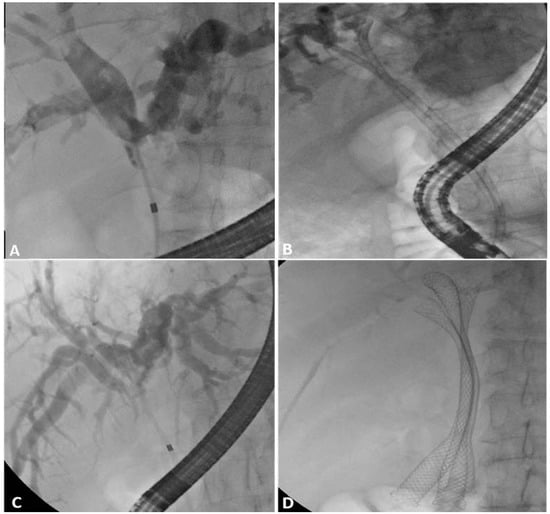

- Boškoski, I.; Tringali, A.; Familiari, P.; Bove, V.; Landi, R.; Attili, F.; Perri, V.; Onder, G.; Mutignani, M.; Costamagna, G. A 17 years retrospective study on multiple metal stents for complex malignant hilar biliary strictures: Survival, stents patency and outcomes of re-interventions for occluded metal stents. Dig. Liver Dis. 2019, 51, 1287–1293. [Google Scholar] [CrossRef] [PubMed]

- Lee, T.H.; Moon, J.H.; Choi, J.-H.; Lee, S.H.; Lee, Y.N.; Paik, W.H.; Jang, D.K.; Cho, B.W.; Yang, J.K.; Hwangbo, Y.; et al. Prospective comparison of endoscopic bilateral stent-in-stent versus stent-by-stent deployment for inoperable advanced malignant hilar biliary stricture. Gastrointest. Endosc. 2019, 90, 222–230. [Google Scholar] [CrossRef] [PubMed]

- Lee, T.H.; Moon, J.H.; Park, S. Biliary stenting for hilar malignant biliary obstruction. Dig. Endosc. 2020, 32, 275–286. [Google Scholar] [CrossRef] [PubMed]